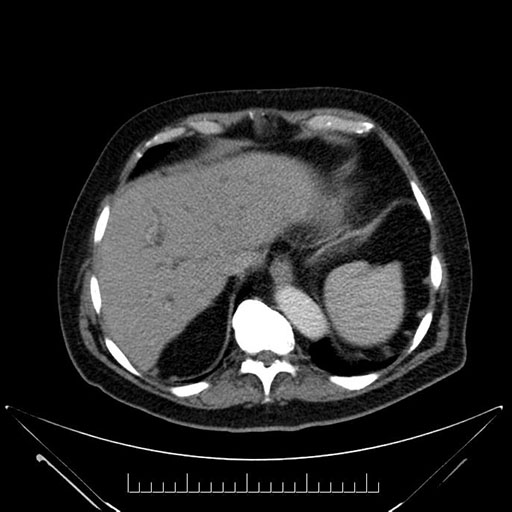

Axial - 3 months prior